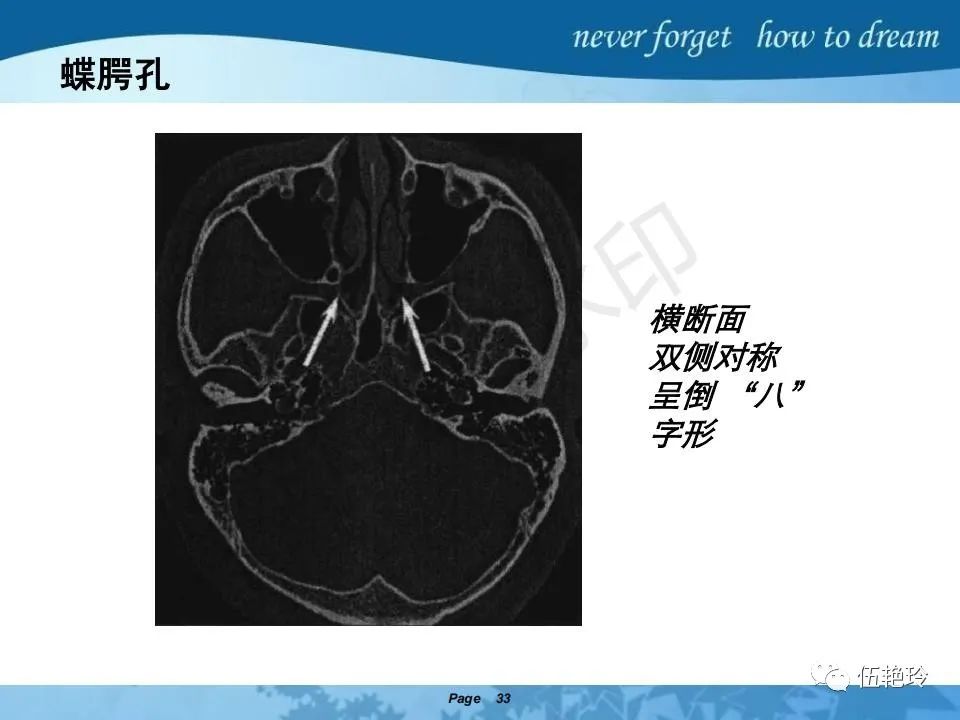

2.31 向上颅内:①鼻咽顶壁→破裂孔(岩尖、斜坡)→蝶窦、海绵窦;②鼻咽顶壁→蝶骨基底部→蝶窦、海绵窦;③鼻咽侧壁→茎突前间隙→蝶骨大翼(卵圆孔)→海绵窦;④鼻咽侧壁→茎突前间隙→翼腭窝→ 颞下窝;⑤鼻咽前壁→鼻腔→翼突、翼腭窝→眶下裂→眶尖→海绵窦;⑥鼻咽前壁→鼻腔→上颌窦、筛窦;